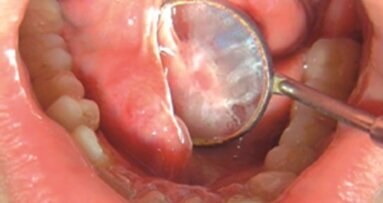

50-letni mężczyzna został skonsultowany w zakresie możliwości wszczepienia implantu w żuchwie po stronie lewej. Historia jego leczenia nie wyróżniała się, ciśnienie krwi oraz tętno pozostawały w granicach normy, rtg klatki piersiowej, EKG, morfologia krwi, osad moczu, badania czynności wątroby i nerek również były w normie. Badanie zewnątrzustne wykazało wyczuwalną z prawej strony śliniankę podżuchwową, a oburęczne badanie palpacyjne dna jamy ustnej w kierunku tylno-przednim wykazało duży, zwarty, niebolesny obrzęk w prawej części dna jamy ustnej w okolicy przewodu ślinianki podżuchwowej (Ryc. 1). Pacjent był nieświadomy obecności obrzęku do momentu wskazania go przez lekarza dentystę. Zdjęcie rtg żuchwy wykonane w projekcji zgryzowej oraz zdjęcie panoramiczne potwierdziło rozpoznanie, przedstawiając rzutującą na zdjęciu strukturę znajdującą się w okolicy prawych przedtrzonowców (Ryc. 2). Wzdłuż jej największej długości mierzyła ok. 1.5 cm.

Miejscowo nałożono żel znieczulający (EMLA) na 5 min, nie podano znieczulenia w zastrzyku. Procedura polegała na odnalezieniu złogów kamienia i wyizolowaniu przewodu ślinianki z otaczających tkanek. Wykorzystano zgłębnik kulkowy, następnie przeprowadzono nacięcie przewodu ślinianki powyżej złogów kamienia, kamień usunięto oraz sprawdzono drożność przewodu (Ryc. 3a i b). Przewód wraz z błoną śluzową jamy ustnej były nacinane do momentu, kiedy złogi kamienia, umiejscowione w obrębie dystalnej części przewodu Whartona na dnie jamy ustnej, odsłoniły się dzięki laserowi Waterlase MD Er;Cr:YSGG o parametrach 2,5 W, 30 pps, w trybie S, używając złotego uchwytu z końcówką Z11.